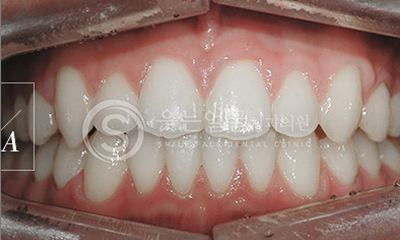

한눈에 보는

치아교정 전후사진